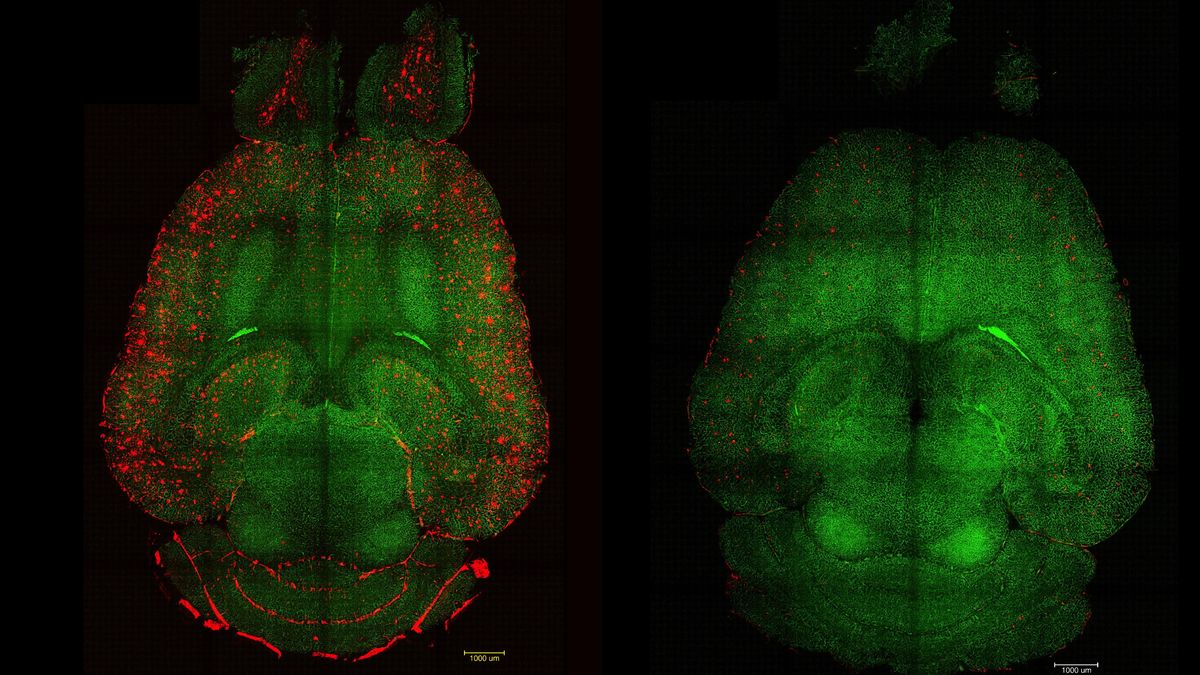

Los investigadores utilizaron modelos de ratón genéticamente programados para producir mayores cantidades de proteína beta-amiloide y desarrollar un deterioro cognitivo significativo similar al Alzheimer. Administraron solo tres dosis de los fármacos supramoleculares y posteriormente monitorizaron regularmente la evolución de la enfermedad.

“Solo una hora después de la inyección, observamos una reducción del 50-60 % en la cantidad de beta-amiloide en el cerebro”, explica Junyang Chen, primer coautor del estudio, investigador del Hospital de China Occidental de la Universidad de Sichuan y estudiante de doctorado del University College de Londres (UCL).

Los datos más impactantes fueron los efectos terapéuticos. Los investigadores realizaron diversos experimentos para analizar el comportamiento de los animales y medir su deterioro de la memoria a lo largo de varios meses, abarcando todas las etapas de la enfermedad. En uno de los experimentos, trataron a un ratón de 12 meses (equivalente a un humano de 60 años) con las nanopartículas y analizaron su comportamiento después de 6 meses. El resultado fue impresionante: el animal, de 18 meses (equivalente a un humano de 90 años), había recuperado el comportamiento de un ratón sano.